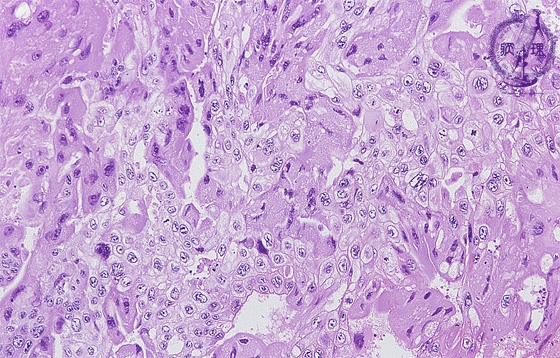

絨毛癌ミクロ像(HE弱拡大)

ミクロ像(HE弱拡大):好酸性で多核の合胞体栄養膜細胞(syncytiotrophoblast、黄色点線)に類似した腫瘍細胞と、淡明な細胞質を有する細胞性栄養膜細胞(cytotrophoblast、青色点線)に類似した腫瘍細胞のシート状増殖が認められる。前者の腫瘍細胞からはh-CGが産生・分泌される。